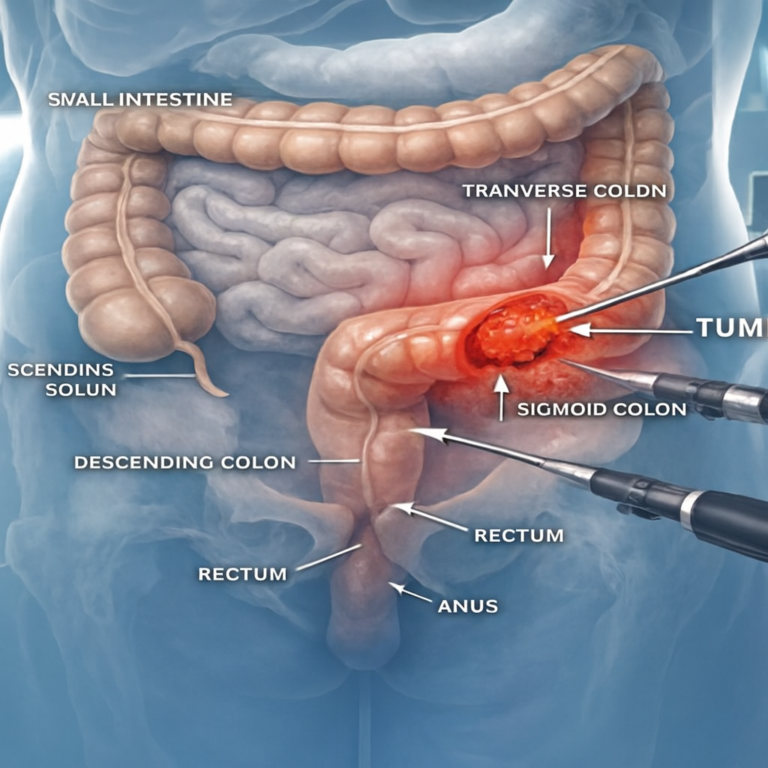

Step into the beginning—where ideas ignite and clarity unfolds Colorectal cancer is one of the leading causes of cancer‑related deaths worldwide, yet…

Introduction Colon cancer surgery in Mira Road, The Colon cancer is one of the most common types of cancer worldwide, and timely…

Best Colorectal Cancer Surgery In Mira Road Understanding What You’re Going Through Colorectal cancer surgery in Mira Road provides advanced treatment options.…

What This Blog Is About If you or someone you love has been dealing with symptoms like blood in the stool, pain…

Understanding What You’re Going Through If you or someone close to you has been diagnosed with colorectal cancer, it’s completely normal to feel…